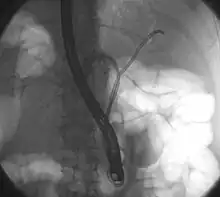

| Klatskin tumor during ERCP. Wires were inserted into the left and right biliary systems. Both parts were injected through a tube with contrast, but there is no contrast visible in the area of confluence of the two systems | |